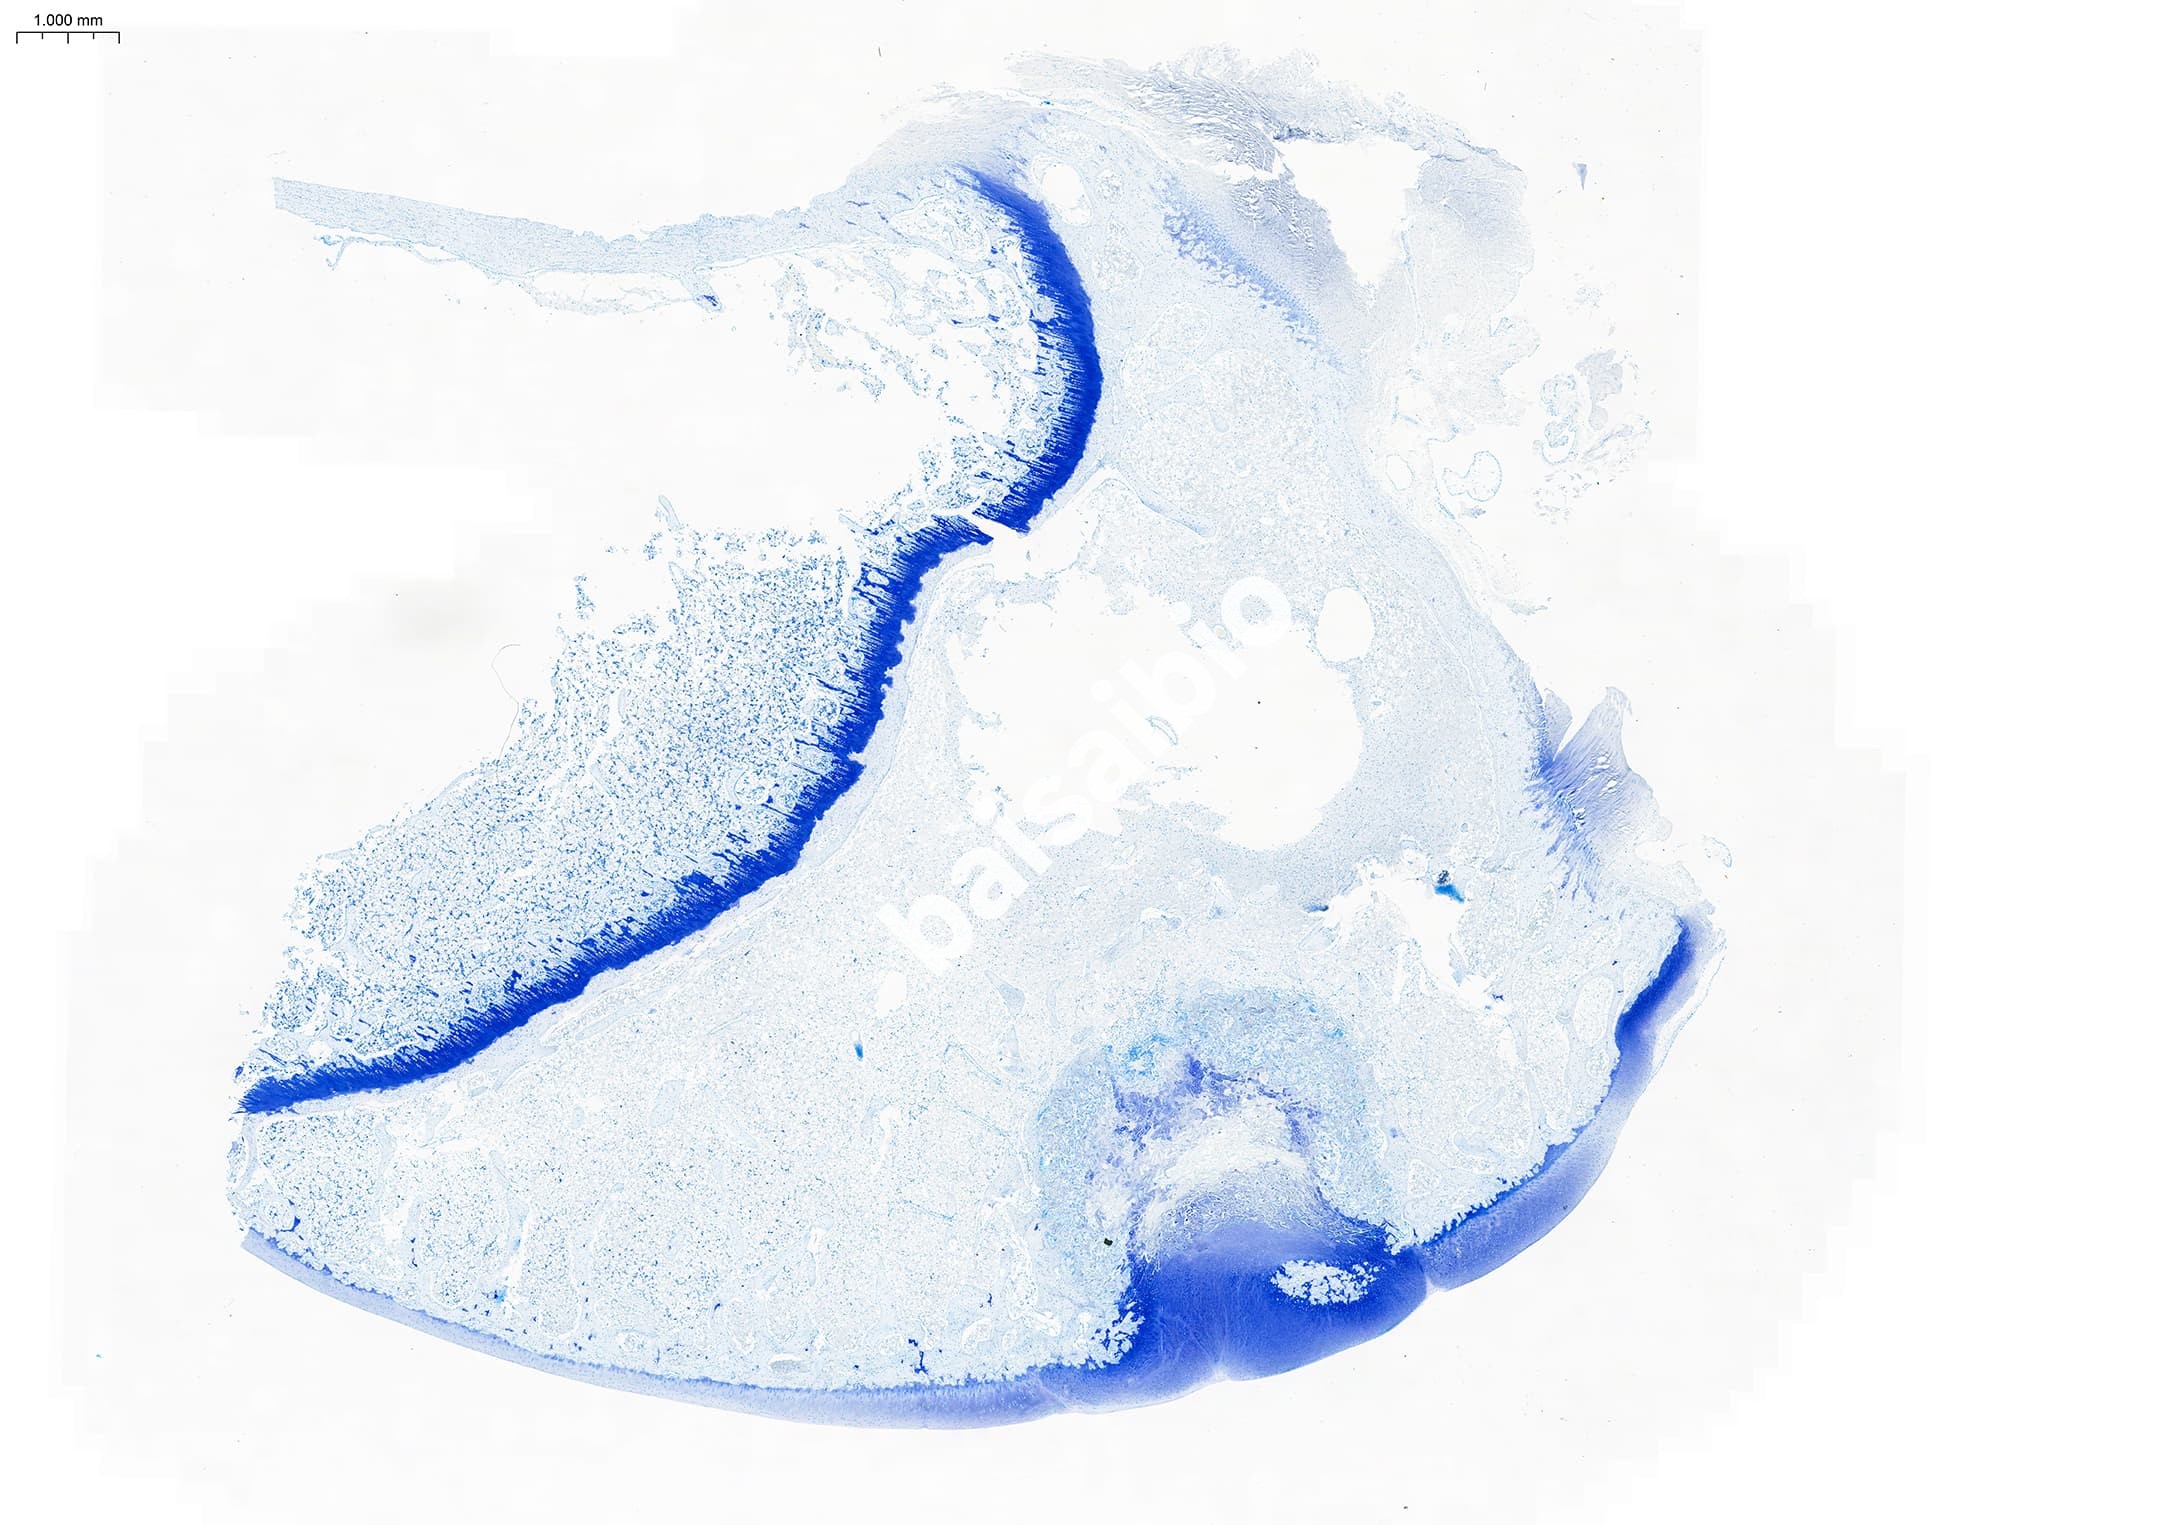

甲苯胺蓝(Toluidine blue)中的阳离子有染色作用,组织细胞的酸性物质与其中的阳离子相结合而被染色。可染细胞核使之呈蓝色;肥大细胞胞质内含有肝素和组织胺等异色性物质遇到甲苯胺蓝可呈异染性紫红色,可用于尖锐湿疣的初筛及肥大检测。

②、石蜡切片染色:烤片-脱蜡至水-甲苯胺蓝染色-分化-脱水透明-中性树胶封片-显微镜下观察

③、冰冻切片染色:水洗包埋剂-甲苯胺蓝染色-分化-脱水透明-中性树胶封片-显微镜下观察